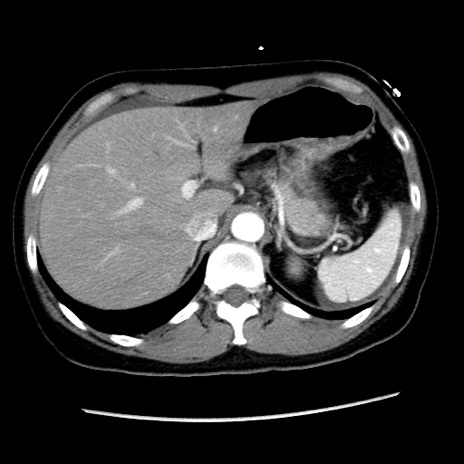

矢状断像